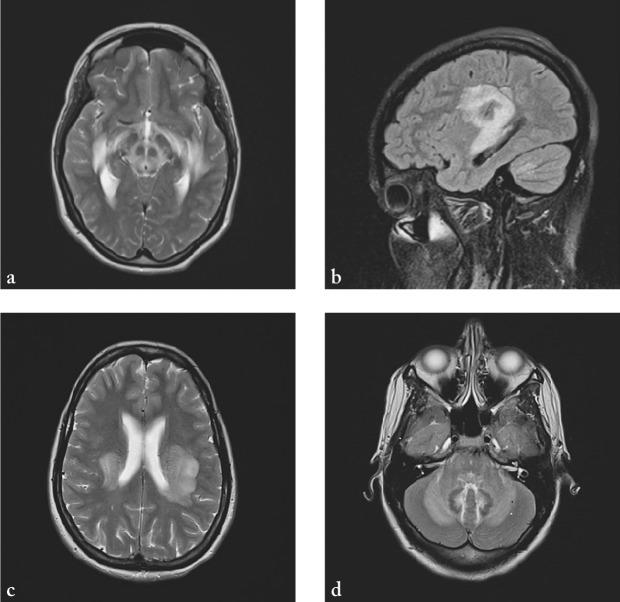

Acute disseminated encephalomyelitis (ADEM) is an inflammatory demyelinating disease of the central nervous system that usually affects children and young adults. It most commonly has a monophasic course, although relapses are reported. Clinical presentation of the disease includes encephalopathy and multifocal neurological deficits. There are no established reliable criteria for diagnosis of ADEM and sometimes it is difficult to distinguish it from first attack of multiple sclerosis, especially in adults. The diagnosis of ADEM is based on clinical, radiological and laboratory findings. In the treatment of ADEM, high doses of corticosteroids, plasmapheresis and immunoglobulins are used. We report a case of a young adult female patient with ADEM who fully recovered after prompt administration of high dose methylprednisolone and immunoglobulins.

急性播散性脑脊髓炎(ADEM)是一种中枢神经系统的炎性脱髓鞘疾病,通常影响儿童和年轻人。虽然有复发的报道,但它最常见的是单相病程。该疾病的临床表现包括脑病和多灶性神经功能缺损。目前尚无公认的可靠诊断急性播散性脑脊髓炎的标准,有时很难将其与多发性硬化症的首次发作区分开来,尤其是在成年人中。急性播散性脑脊髓炎的诊断基于临床、影像学和实验室检查结果。在急性播散性脑脊髓炎的治疗中,使用高剂量的皮质类固醇、血浆置换和免疫球蛋白。我们报告一例患有急性播散性脑脊髓炎的年轻成年女性患者,在迅速给予高剂量甲泼尼龙和免疫球蛋白后完全康复。